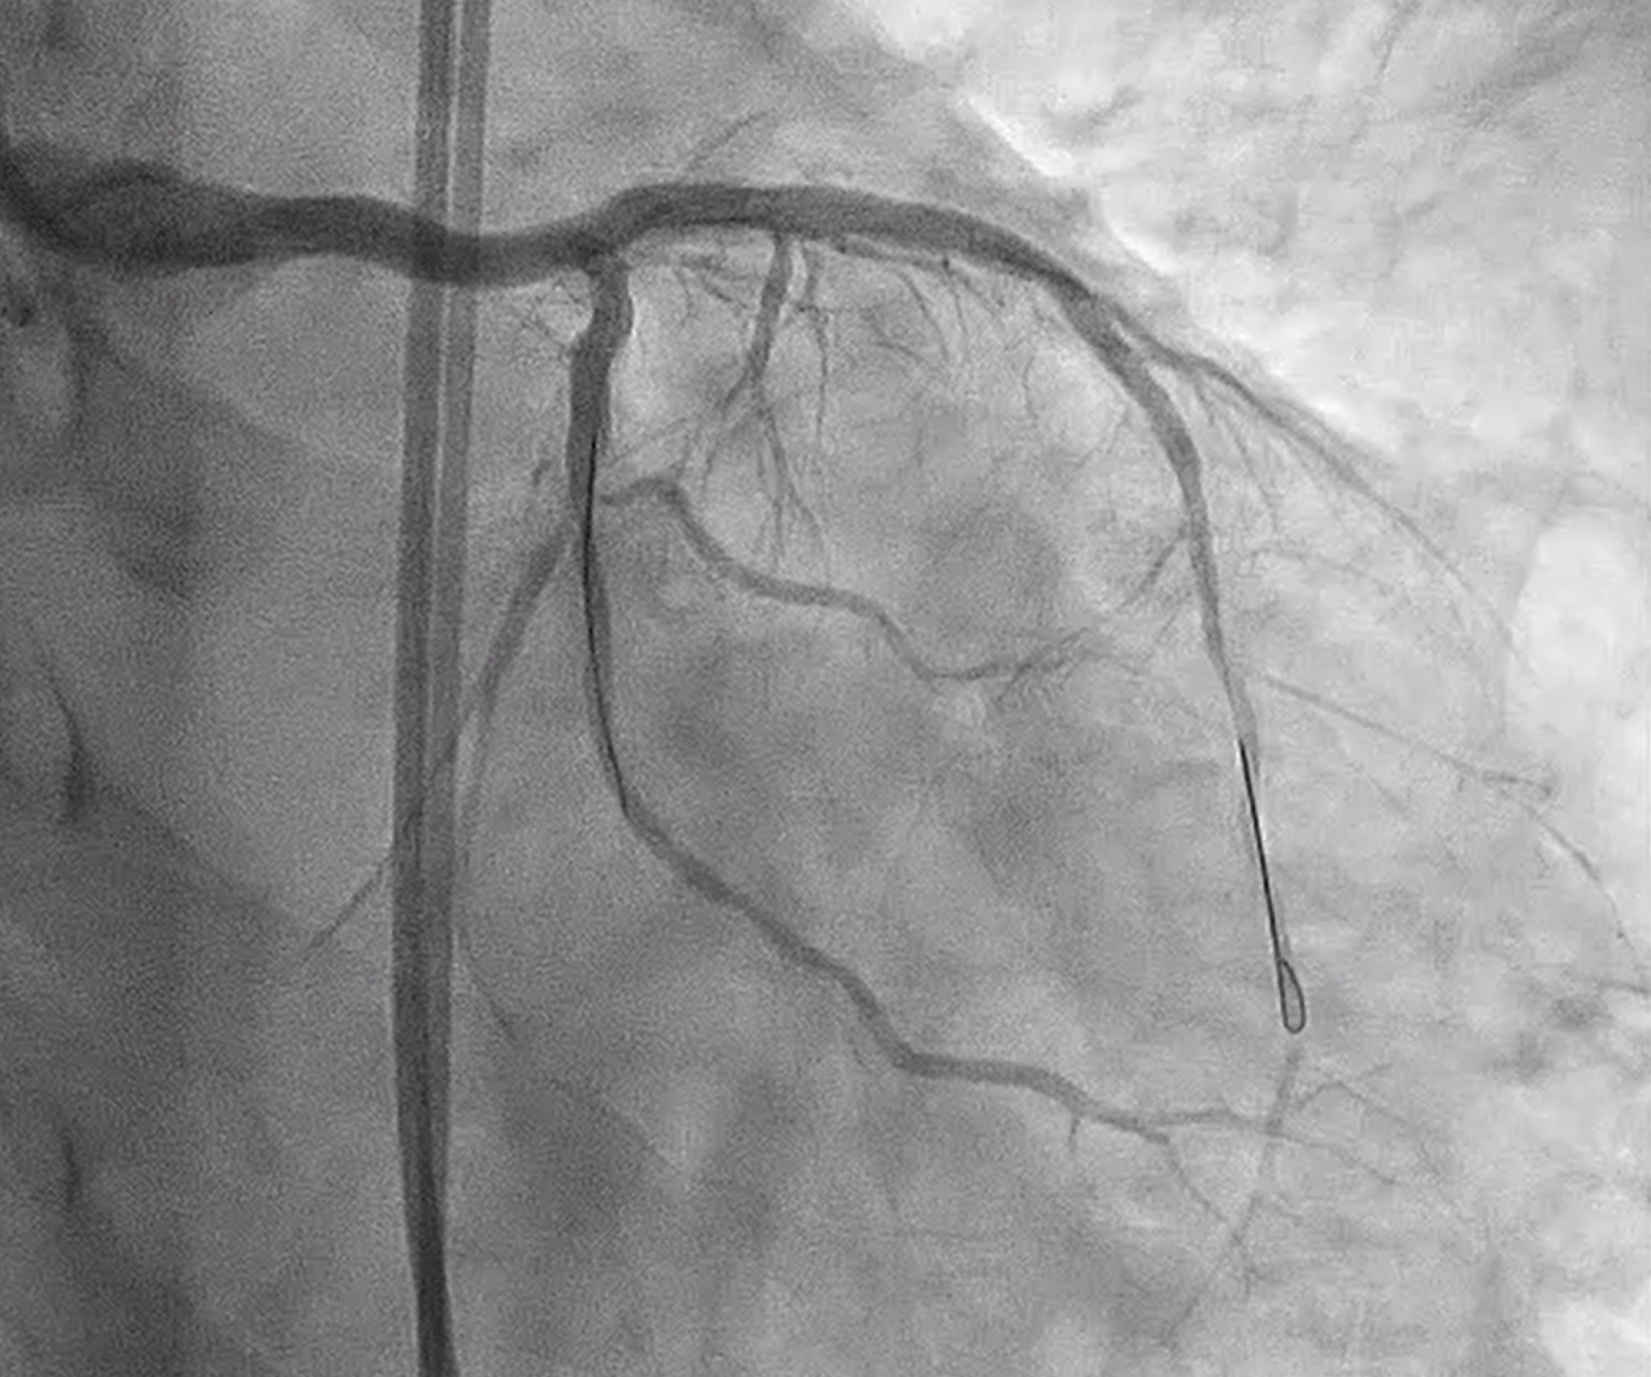

We performed PCI at CTO LAD and LCx with contralateral injection with antegrade wiring and upfront rotablation at LM, LAD and LCx due to heavily calcified lesion. The 7 Fr EBU 3.5 and 6 Fr JR 4.0 catheter were engaged into LCA and RCA, respectively. We opened the LCx CTO segment using microcatheter with Fielder XT guidewire (GW) then rewire from LCx to distal LAD. The CTO GW was exchange to RotaWire Floppy. Rotablation was done at LM-mid LAD with Burr 1.5 mm and LM-proximal LCx with Burr 1.5 mm. IVUS showed EEL of mid LAD = 2.5 mm, proximal LAD = 4.0 mm, distal LM = 5.5 mm and proximal LCx = 3.5 mm. The lesion of mid LAD was prepared with scoring balloon 2.0/15 mm and LM-proximal LAD with scoring balloon 3.5/15 mm. A 2.5/33 mm stent was deployed from proximal-mid LAD. We decided to stenting the lesion at proximal LCx before stenting the lesion at LM-proximal LAD using provisional one stent and POT-kiss-POT technique. A 3.0/26 mm stent was deployed at proximal LCx. A 3.5/38 mm stent was deployed from distal LM-proximal LAD and 3.5/13 mm stent from ostial LM-distal LM. POT was done with a non-compliance (NC) 5.0/12 mm balloon along LM stent. Kissing balloon inflation with NC 3.0/15 mm balloon at LM-LCx and 3.5/15 mm balloon at LM-LAD then final POT with NC 5.0/12 mm was done. IVUS showed well stent expansion, no malapposition and no stent edge dissection. The patient had no re-admission. Echocardiography after 3 months showed significant improvement of LV function to 56%.

CINE final A.mp4